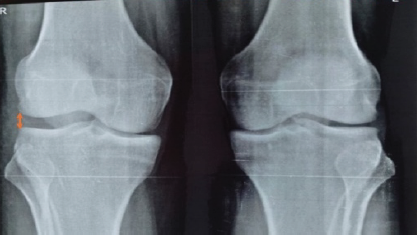

An Anomalous Attachment of the Medial Meniscus Posterior and Anterior Roots Mimicking a Bucket Handle Meniscus Tear: A Case Report and Review of the Literature

Alexander J. Egol , Bradley A. Lezak , Emily Berzolla , Spencer M. Stein